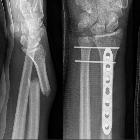

Galeazzi fracture-dislocation

Galeazzi fracture-dislocations consist of fracture of the distal part of the radius with dislocation of distal radioulnar joint and an intact ulna. A Galeazzi-equivalent fracture is a distal radial fracture with a distal ulnar physeal fracture .

Plain radiograph

A forearm series is usually sufficient for diagnosis and management planning. However, good quality orthogonal views are needed to identify and characterize displacement correctly. Features include:

- radial shaft fracture

- commonly at the junction of the middle and distal third

- dorsal angulation

- dislocation of the distal radioulnar joint

- radial shortening may occur, and if greater than 10 mm, suggests complete disruption of the interosseous membrane

These fractures are unstable and operative fixation is usually required to reduce and fix the radial fracture, with arm immobilization in pronation . The exact mode of fixation depends on the location of the radial fracture :

- diaphysis: elastic nail

- metaphyseal-diaphyseal junction: plate and screw

- distal radius: Kirschner wires (K-wires)